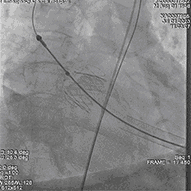

释放J-valve29#瓣膜:

复查根部造影,未见明显反流,瓣膜形态和位置满意,双侧冠脉显影良好: